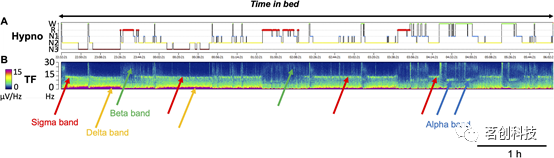

对于仅仅依靠EEG而不使用EOG或EMG来进行睡眠分期的问题,不仅从生理和技术角度来看(EEG信号是否包含足够的信息来区分警觉状态,我们是否能够提取和解读这些信息?)很重要,而且从实践的角度来看也很重要,特别是在长期VideoEEG监测的背景下,以及可穿戴家用设备的开发。从EEG信号中提取的信息还可以获得有关睡眠结构的关键信息,目前大多数睡眠分析软件所实现的时频分析仅基于EEG信息,通过EEG频率、EEG功率和时间的三维函数来识别整晚睡眠过程中EEG的动态变化(图3)。

图3.睡眠记录期间的EEG时频分析。